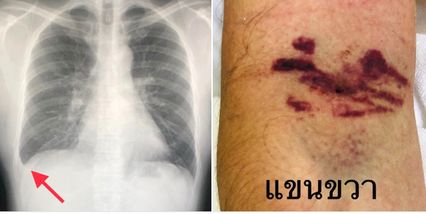

ต่อมาวันที่ 28 พ.ย.66 ผู้ป่วยยังมีไข้ เหนื่อย กินอาหารได้น้อย ปัสสาวะออกน้อย ผลตรวจร่างกาย ระดับออกซิเจนที่ปลายนิ้ว 97% และมีจุดเลือดออกตามแขนขา เจาะเลือด Hct 46.3% เม็ดเลือดขาวต่ำ 2,880 เกล็ดเลือดลดลงเหลือ 4,000  ค่าเอนไซม์ตับขึ้น SGOT 137, SGPT 97, GGT 452 เอกซเรย์ปอดมีน้ำในเยื่อหุ้มปอดข้างขวาเล็กน้อย ผู้ป่วยมีเลือดออกง่าย เห็นจ้ำเลือดที่แขนขวาบริเวณที่ถูกเจาะเลือด

แพทย์วินิจฉัยสรุปว่า ผู้ป่วยเป็นไข้เลือดออกเดงกี เกล็ดเลือดต่ำมากเหลือเพียง 4,000  มีการรั่วของพลาสมาออกนอกหลอดเลือด ทำให้ความเข้มข้นของเลือดเพิ่มขึ้นเป็น 46.3% และทำให้มีน้ำในเยื่อหุ้มปอด มีอาการเหนื่อย

ทั้งนี้หลังให้น้ำเกลือ เกล็ดเลือด 1 ยูนิต และพลาสมา 2 ยูนิต ผู้ป่วยอาการดีขึ้น ไข้ลง กินอาหารได้ ปัสสาวะออกมากขึ้น เหนื่อยน้อยลง ความเข้มข้นของเลือด Hct ลดลงเหลือ 40.8% เกล็ดเลือดเพิ่มขึ้นเป็น 98,000  เอกซเรย์ปอดดีขึ้น หลังนอนรักษาในโรงพยาบาลนาน 4 วัน แพทย์อนุญาตให้กลับบ้านได้